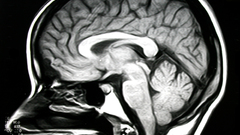

brain

Organ that controls the nervous system in vertebrates and most invertebrates

A brain is an organ that serves as the center of the nervous system in all vertebrate and most invertebrate animals. It is located in the head, usually close to the sensory organs for senses such as vision. It is the most complex organ in a vertebrate's body. In a human, the cerebral cortex contains approximately 14–16 billion neurons, and the estimated number of neurons in the cerebellum is 55–70 billion. Each neuron is connected by synapses to several thousand other neurons. These neurons typically communicate with one another by means of long fibers called axons, which carry trains of signal pulses called action potentials to distant parts of the brain or body targeting specific recipient cells.